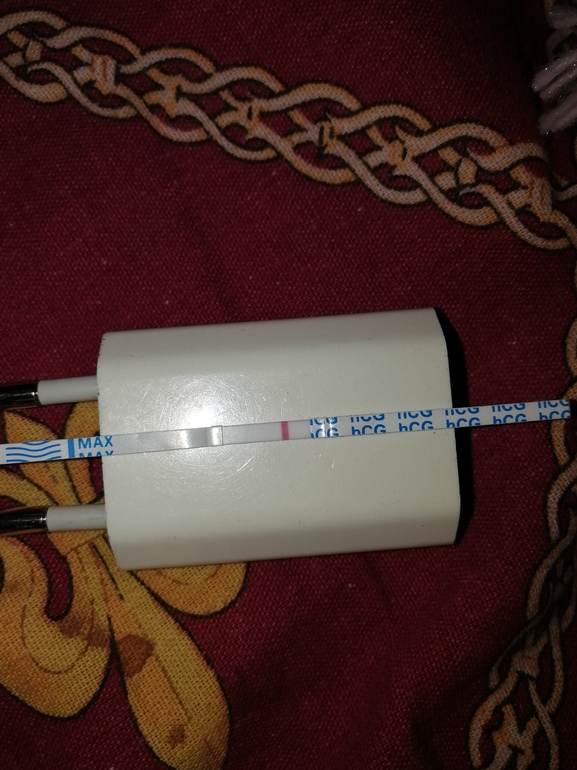

По тестам она должна быть завтра/послезавтра (тест скорей всего завтра будет положительный)

Тесты не информативны на О. Они в любом случае будут яркими. Тем более тут не ЛГ лопает фоллик, а ХГЧ. У меня они яркие до сих пор, хотя уже 3 ДПУ. И не факт, что ЛЯ совулировал. Лучше не тратьтесь на тесты на О, а купите побольше на Б. Так клево наблюдать, как выходит укол и ярчает св й ХГЧ)

Я тест сделал перед уколом)

А у меня перед уколом и почти сутки после него тест на О был отрицательный, через сутки начал ярчать, произошла О в ПЯ, ещё один укол и только после него выдал настоящий положительный результат и так три дня держался.

Не тратьте тесты, после укола они всегда положительные, реагируют на хгч. Сходите через пару дней на узи и гляньте, была ли О.

Кстати, только что тест на Б сделала, укол то второй всего 3 дня назад был, а тест уже чистый... Как так?